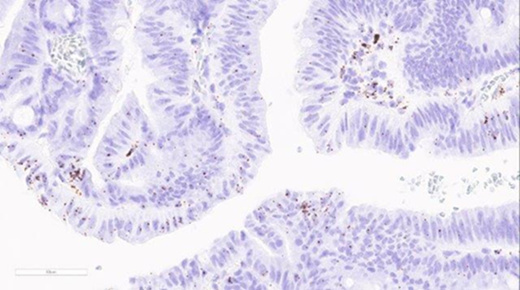

ACD's RNAscope assays represent a major technological advance for in situ RNA detection. For the first time, robust single RNA molecule detection is available for formalin-fixed, paraffin-embedded (FFPE) tissue. Since their commercialization three years ago, these assays have been adopted across the globe by major pharma biotech companies and leading research institutions for drug discovery, translational research, and the development of clinical and companion diagnostic tests. The RNAscope LS assays are fully automated on the BOND RX platform. This open and flexible system automates staining to provide a fast, high-throughput workflow with exceptional consistency and minimal hands-on time.